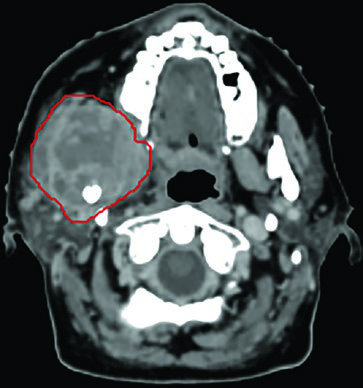

An illustrative case is an 83-year-old woman, previously treated surgically for right tongue squamous cell carcinoma, who presented 3 years later with a painful right level II nodal mass deep to the parotid, extending into the parapharyngeal space and carotid sheath. She was not a candidate for radical chemoradiation and received 45 Gy in 5 fractions, twice weekly. GTV delineation (red) was aided by CT-MRI fusion, with CT on the left and MRI on the right displayed on the same planning screen.

While her pain improved, MRI at 4 months showed possible progression on T1 but response on T2 — discordant findings that could lead to a premature salvage decision if interpreted in isolation. At 9 months, MRI demonstrated disease stability and the patient was pain-free. This case reinforces that multiparametric assessment and patience are essential in post-SBRT follow-up.